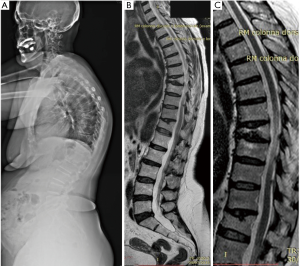

All the nine patients were in theory suitable for corpectomy and expandable titanium cage implant (7). But this approach was performed only in two of them. In fact, in 7 patients, a reconstruction of the anterior and medial spinal column was accomplished by third generation percutaneous vertebral augmentation systems (MK). In all the cases however a posterior fixation with rod and screws was always performed. The choice between one technique and the other one was made according to the signal in short tau inversion recovery (STIR) in the MRI sequences: in case of hyperintense signal to the level of the collapsed vertebra (VP), we decided for the percutaneous vertebral augmentation (Figures 3,4) (8). In absence or in case of very low STIR hyperintense signal, we chose for the standard corpectomy (Figures 5,6). Indeed, the presence of positive signal in the VP is in fact indicative of the reducibility of the vertebral soma. Moreover, in the cases of spinal canal compression the applicability of the third generation MK alone, without any posterior decompression, must not be excluded: it must be inferior to 1/3 and 2/3 respectively in case of fractures level above and below the spinal cord and any clinical signs of radicular compressions must not be identified. Otherwise, a direct posterior spinal cord decompression must be performed. Furthermore it is mandatory to evaluate the state of the anterior longitudinal ligament (ALL). In case of ossification of ALL at the level of the VP, MK has to be avoided, because a satisfactory correction of the vertebral height and a substantial management of the regional deformity might not be achieved. Mean follow-up was 18 months (range, 12–28 months). None of the patients experienced neurologic deterioration neither they showed a progression of local or regional deformity. No infections, dural tears, or spinal cord injuries occurred. No revision surgery was performed. In case of corpectomy the main blood loss and the mean surgical time were inevitably greater (9).